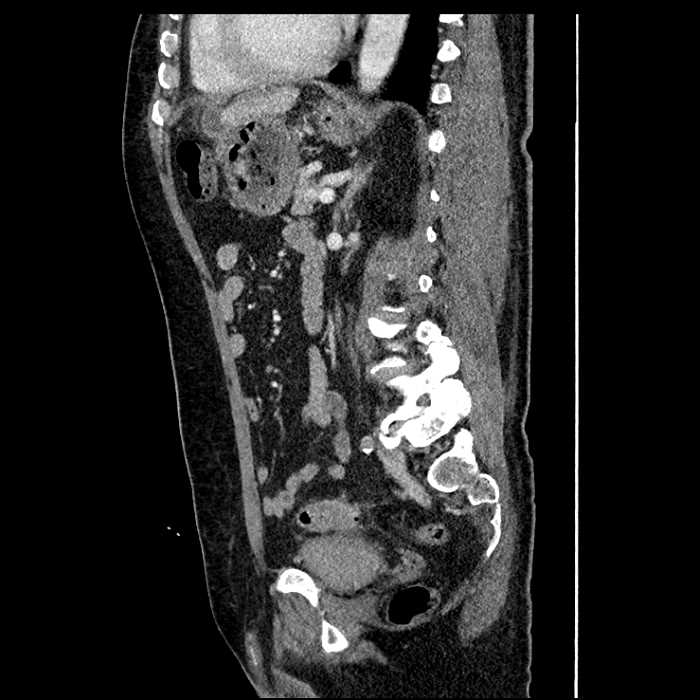

• Large fluid density structure in hepatic segments 7 and 8 measuring 10 x 7 x 7 cm with internal septation and circumferential ill-defined low density compatible with edema

• Peripherally enhancing subcapsular collections along the anterior margin of the left hepatic lobe measuring 3 x 1 cm and 2 x 1 cm

• Clearly marginated fluid density structure in segment 7 and several other scattered tiny hypodensities, which likely represent cysts

• Hepatic abscess

Acute sigmoid diverticulitis complicated by a small contained perforation and a large abscess in the right hepatic lobe. Additional small subcapsular abscesses along the anterior margin of the left hepatic lobe.

Additionally, loss of the normal fat plane between the peridiverticular collection and adjacent thickened loops of small bowel raises the potential for an enterocolonic fistula.

• The classic CT imaging appearance is a double target sign with internal low density surrounded by an internal enhancing rim (capsule) and a low density external rim (edema)

Hepatic abscess showing the double target sign with low density internally surrounded by a thin inner enhancing rim (red arrow) and ill-defined outer low density rim (yellow arrow). Blue arrow indicates an internal septation. Red arrows: additional smaller subcapsular abscesses. Red arrow: focal contained perforation associated with diverticulitis.